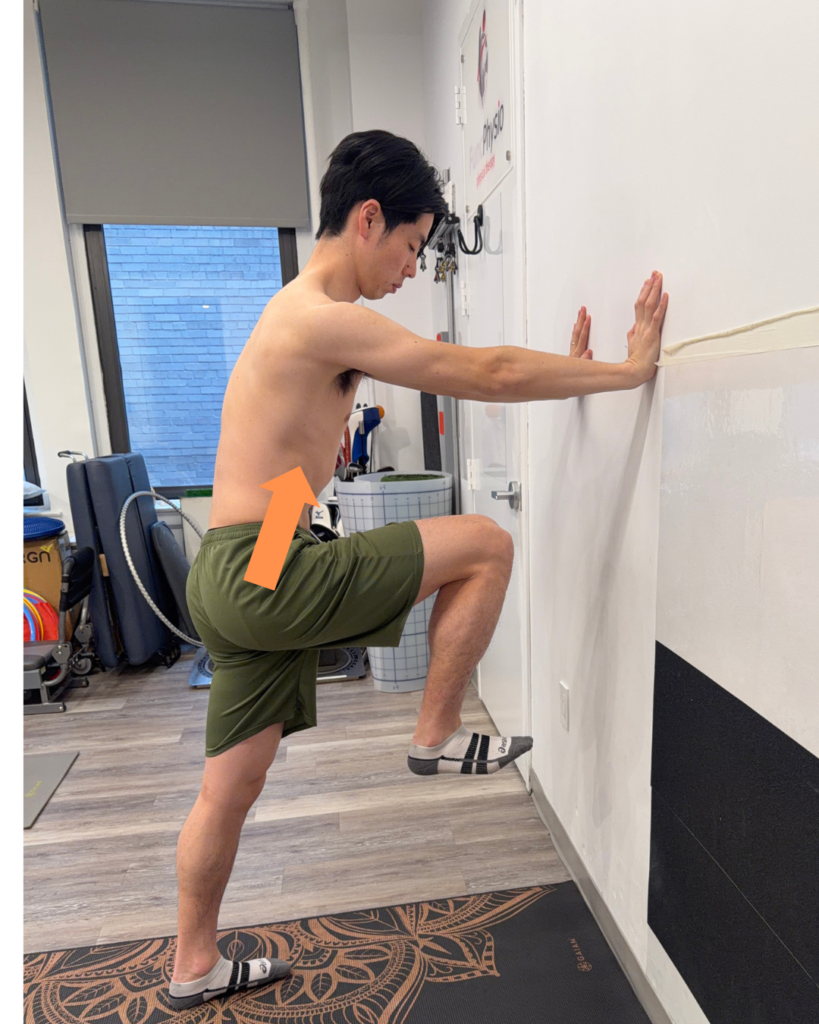

1. Anterior Elevation Exercise: High Stepping

Goal: Improve pelvic lift and forward drive during swing phase

How to perform:

- Stand tall

- Lift one knee toward your chest in a marching motion

- Focus on initiating the movement from the pelvis

- Alternate sides with control

- Be aware of stand leg posterior depression

Goal:

- Improve foot clearance

- Reduce compensations like trunk leaning